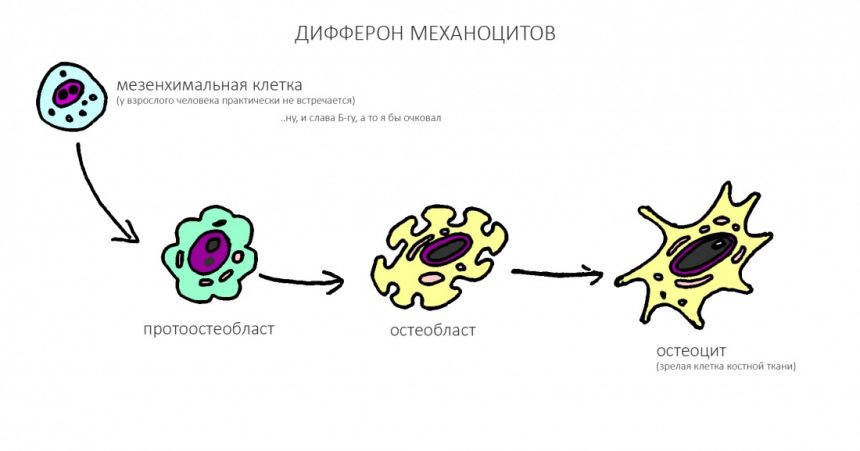

Пролиферация, последняя фаза послеоперационного воспалительного процесса, характеризуется усилением деления клеток и, как следствие, регенерацией поврежденных тканей. Если мы говорим именно о костной ткани челюстей, то на клеточном уровне это происходит следующим образом:

Как вы успели заметить, мезенхимальных клеток, к счастью, у нормального половозрелого человека, к счастью, почти нет. Почему к счастью? Потому, что эти малодифференцированные клетки весьма нестабильны и могут превратиться в любую хрень. В злокачественную опухоль, например.

Ну и, Капитан Очевидность подсказывает нам, что клетки костной ткани, остеоциты и остеобласты, проще и быстрее получаются только из клеток костной ткани — остеобластов. Этот базовый принцип клеточной теории еще в девятнадцатом веке сформулировал немецкий учёный Рудольф Вирхов:

Omni cellula a cellula! (лат. — «Клетка от клетки!»)

а сейчас вам об этом расскажет любой студент медицинского вуза, не забывший гистологию и биологию.